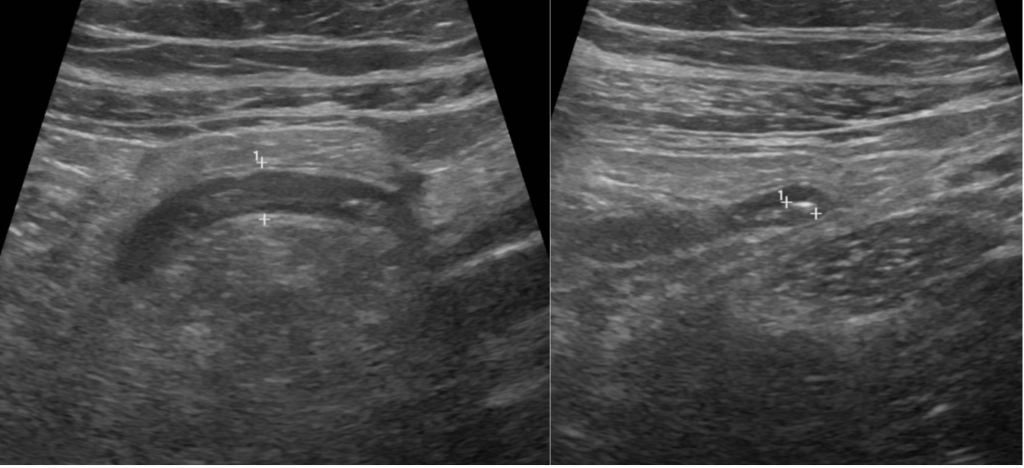

Student Image Challenge 87April 12, 2021The ultrasound diagnosis of ovarian torsion [May 2021]April 28, 2021 Student Image Challenge 88 Student Image Challenge #88 1 / 1 Student Image Challenge #88 A 56 year old male had an episode of acute pancreatitis 5 weeks prior to this endoscopic ultrasound. What is the correct term for this peripancreatic collection? pseudocyst acute peripancreatic fluid collection acute necrotic collection walled-off necrosis phlegmon Incorrect ....Please see the correct answer highlighted Correct: walled-off necrosis EUS shows a circumscribed anechogenic fluid collection with hyperechogenic detritus inside and a clear delineation of the wall. Your score isThe average score is 56% LinkedIn Facebook VKontakte 0% Restart quiz Case courtesy of Prof Adrian Saftoiu EFSUMBAdmin Related postsStudent Image Challenge 111Read more Comments are closed.